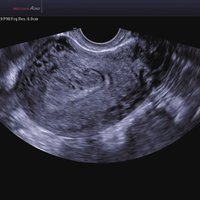

Das Samsung Accuvix A30 ist ein hochwertiges Ultraschallsystem, das mit seiner 3D-Technologie herausragende Ergebnisse ermöglicht. Das Sonographiegerät besitzt 5 Sondenanschlüsse und ist mit 20 unterschiedlichen Schallköpfen kompatibel. Mit dem A30 können Schallköpfe vom Typ Konvex, Mikrokonvex, 3D-Konvex, CW, Phased Array, Linear und Endokavitär verwendet werden. Bei zwei der Sonden handelt es sich um S-VUE Ultraschallsonden, die durch ihre höhere Bandbreite noch feinere Scans erzeugen.

Das Ultraschallsystem hebt sich besonders durch seine 3D-Technologie wie die Face Auto Detection für detaillierte Ultraschallbilder von Föten oder das Volume Shade Imaging, das sich auf die lebensnahe Darstellung von Schattierungen und Hauttönen fokussiert, ab. Mit weiteren wertvollen Technologien wie dem ElastoScan™ werden Tumore schneller erfasst und durch die HD Volumen Bildgebung sowie das DMR+™ eine erstklassige Bildqualität erzielt.

• FAD™, die Face Auto Detection, stellt das Gesicht eines Fötus besonders detailliert dar. Überflüssige Daten werden entfernt und ein besonders realistisches Bild gezeichnet.